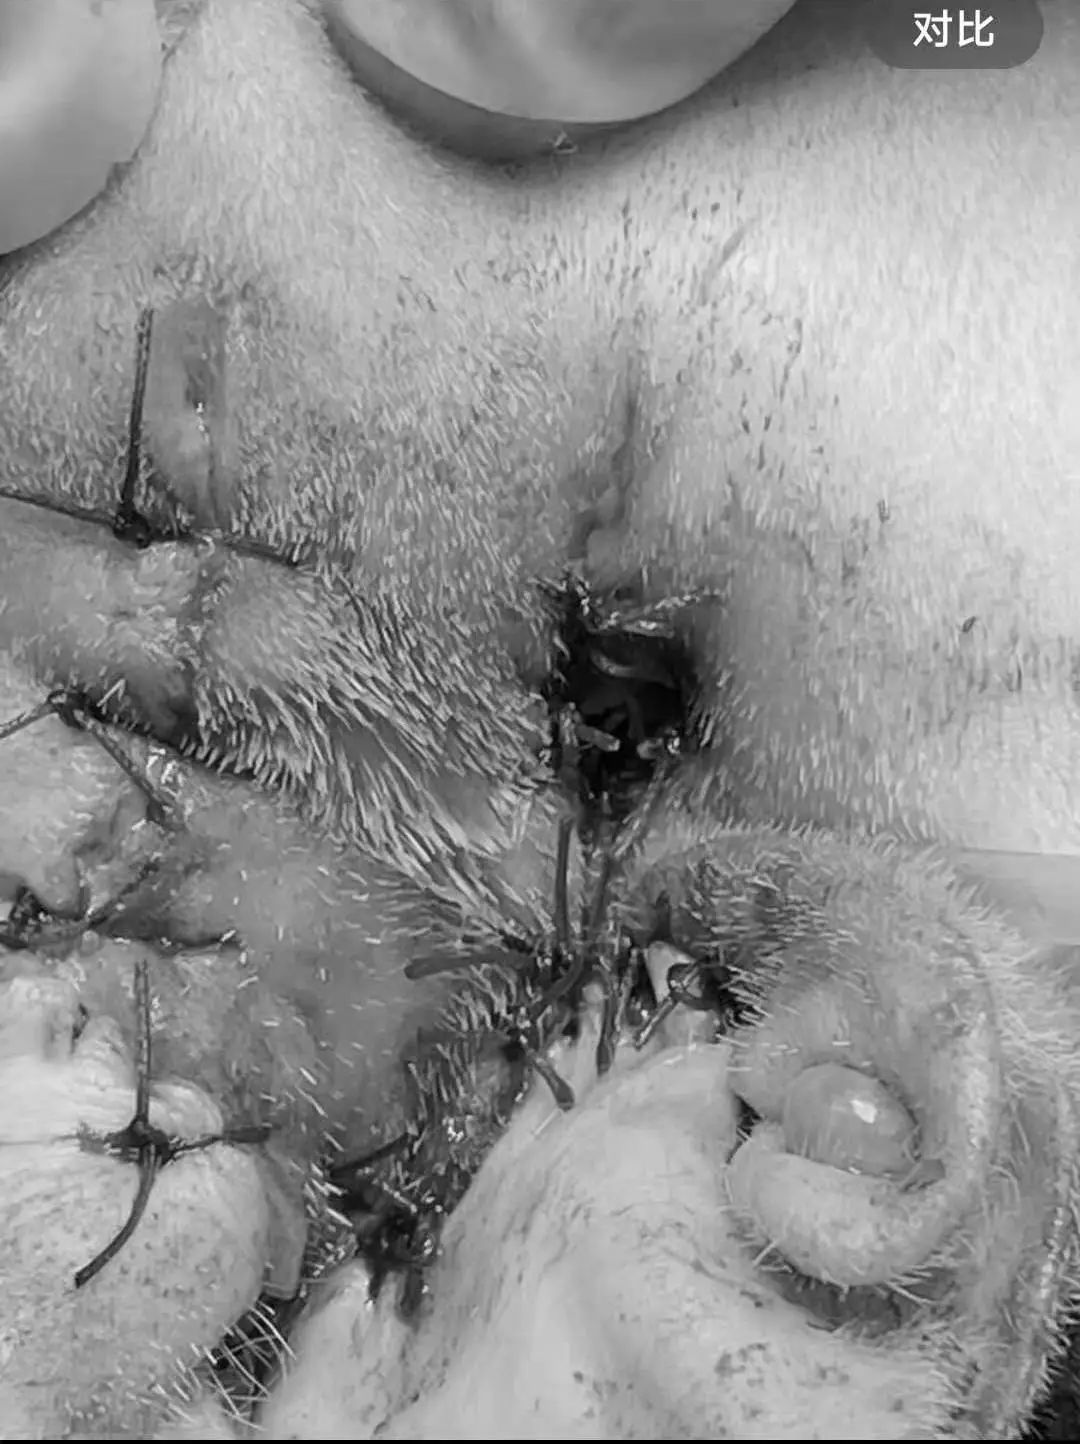

猫咪常年耳朵流脓,经过在其他医院核磁检查在我院进行了垂直耳道切除术,希望早日康复吧↓↓